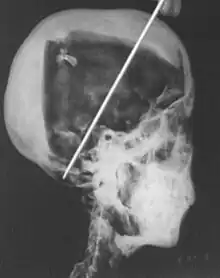

1968 x-rays

An X-ray of Tutankhamun's head showing two levels of resin inside the skull

In 1968 R. G. Harrison, a professor of anatomy, used a portable x-ray machine to re-examine the mummy of Tutankhamun. Harrison quickly discovered that Carter had dismembered the mummy, something that is not mentioned in his publication. The mummy, surrounded by cotton wool and secured by modern bandages, had deteriorated since last photographed by Carter's team in 1926. The beaded skull-cap had disappeared, as had most of the skin on the head; the eyes appeared to be wide open, and the ears were largely destroyed. The beaded collar was gone, as was the front wall of the king's chest; stray beads from this necklace were seen scattered in the torso on the x-rays. The limbs had been moved and further disarticulated, with the left hand and thumb of the right hand found in the sand under the body.[80][81] Although not mentioned by Harrison, the king's penis was also missing.[81] The additional damage to the mummy and the removal of the skullcap and collar likely occurred during World War II,[60] and components suggested to be from the collar have since appeared on the antiquities market.[82]

The x-rays revealed two levels of resin inside the skull. One was introduced when the body was lying on its back, pooling at the back of the head; the other when the head was tilted far back, settling at the top of the skull. Also present in the skull cavity were small bone fragments which Harrison initially believed to be the result of the embalming process. The fact that skull fragments were discovered led many to assume the king was murdered by a blow to the head, but the X-ray could not support or discredit this theory. His age at death was again estimated to be around 18, with a projected height in life of 168.9 centimetres (5 ft 6.5 in).[80] Serological analysis undertaken by the same team determined that Tutankhamun and the KV55 mummy had the same blood group, further indicating a familial relationship.[83]